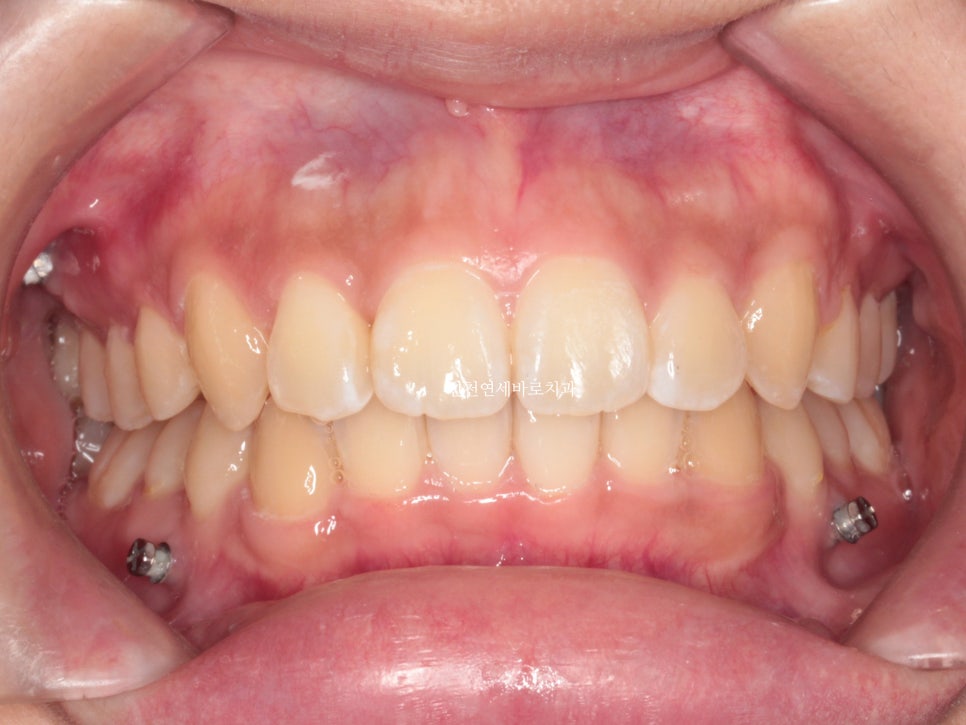

위아래 덧니가 있었고, 깊이 물리는 과개교합 및 중심선의 불일치 보이고 있습니다.

미니스크류를 총 6개 식립했던 환자분입니다.

골격에 대한 분석 후 위쪽 치열은 후방 + 상방 으로 당겼습니다.

치료가 마무리 되던 날 찍은 사진입니다.

미니스크류 = 나사는 유지목적으로 1년정도 유지하다가 제거했습니다.